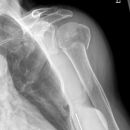

Pseudarthrose